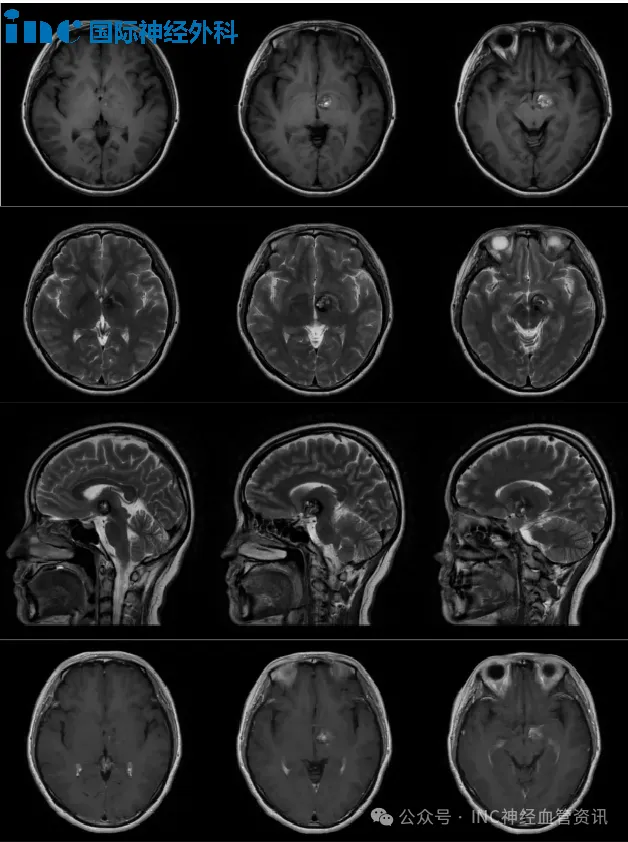

当孩子的体检报告或诊断书上出现脑海绵状血管瘤时,许多家长都会感到迷茫和焦虑。这病严不严重?要不要手术?手术风险大吗?特别是当孩子已经出现癫痫发作时,手术能根治吗? 此前,...